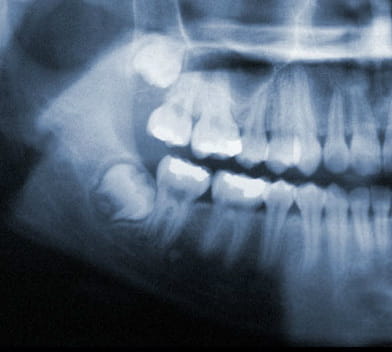

Wisdom Tooth Development

Wisdom teeth generally begin to form in your pre-teen years. By late teen years, the crown of the wisdom teeth will begin to erupt through the gums if there is adequate room. By mid twenties, your wisdom teeth will either be able to fully erupt or will have become impacted. Early removal of wisdom teeth makes the procedure easier for the patient to tolerate and promotes faster healing after wards. By your early forties, the wisdom teeth roots have become fully anchored to the jawbone and if required to be extracted, will be much harder and will need more time to heal.

Wisdom teeth also known as third molars are the last teeth to erupt into the mouth. Wisdom teeth typically appear around a person's mid-twenties but can erupt much later. If wisdom teeth don't have enough space symptoms can occur. The wisdom teeth may only partially erupt or might not come through at all. Dentists designate wisdom teeth 'impacted' if they are wholly or partly blocked from eruption into the mouth. The tooth may lie at an angle and remain tipped against an adjacent tooth. Impacted wisdom teeth can cause problems like pain and swelling; The mouth could ache when stretched open wide or it may be difficult to open your mouth. Tenderness when chewing and biting may occur. Earaches may develop from the spread of pain in the mouth. Symptoms may be intermittent but can begin anytime without warning. If you are experiencing symptoms, it is best to get treatment 'usually removal' as soon as you can to avoid potentially expensive and painful complications.